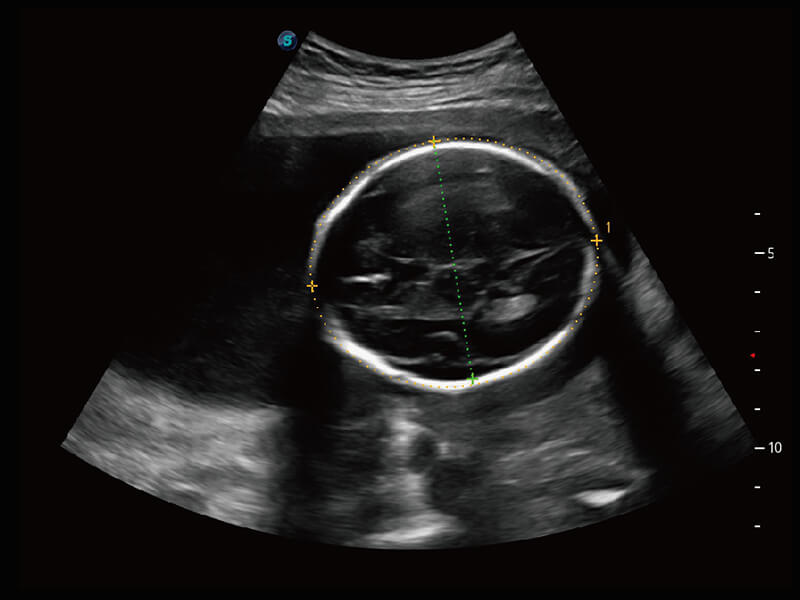

S60探头工艺,从前端信号处理每一个环节采集无损声学数据,真实还原组织原貌,再现解剖细节。